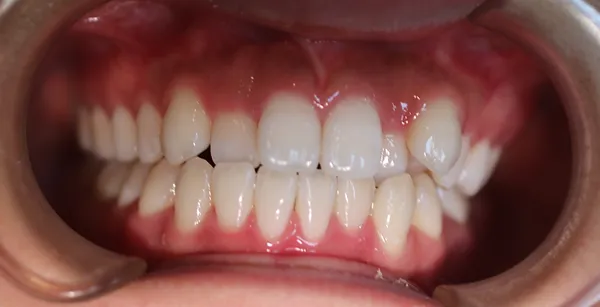

1矯正・マウスピース【治療例2】

治療後